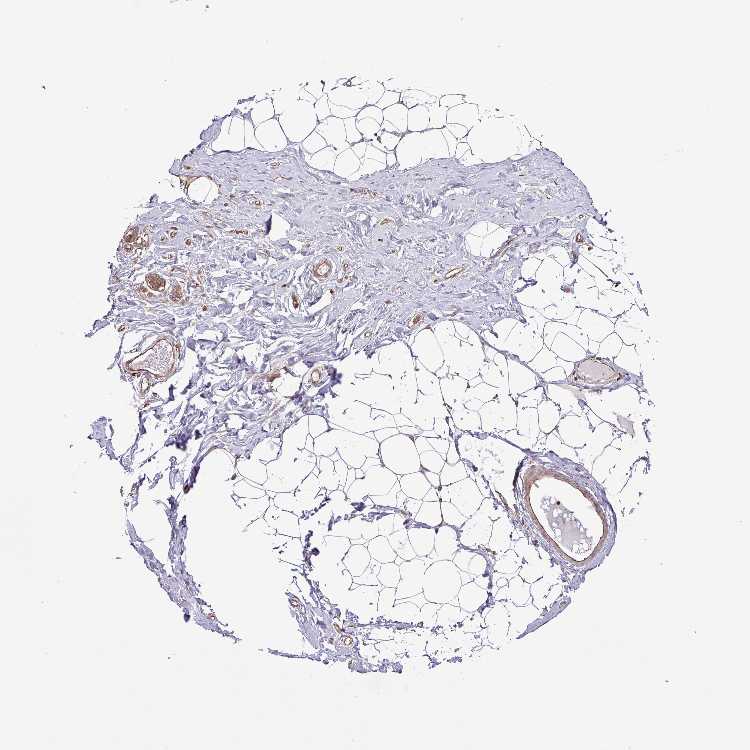

BREAST - Antibody stainingi

Antibody staining in the annotated cell types in the current human tissue is reported as not detected, low, medium, or high, based on conventional immunohistochemistry profiling in selected tissues. This score is based on the combination of the staining intensity and fraction of stained cells.

Each image is clickable and will lead to virtual microscopy that enables deeper exploration of all samples and also displays staining intensity scores, fraction scores and subcellular localization as well as patient and tissue information for each sample.

Antibody HPA047016Antibody HPA051683Antibody CAB005085

Adipocytes Not detectedNot detectedLow

Glandular cells Not detectedHighMedium

Myoepithelial cells Not detectedHighNot detected